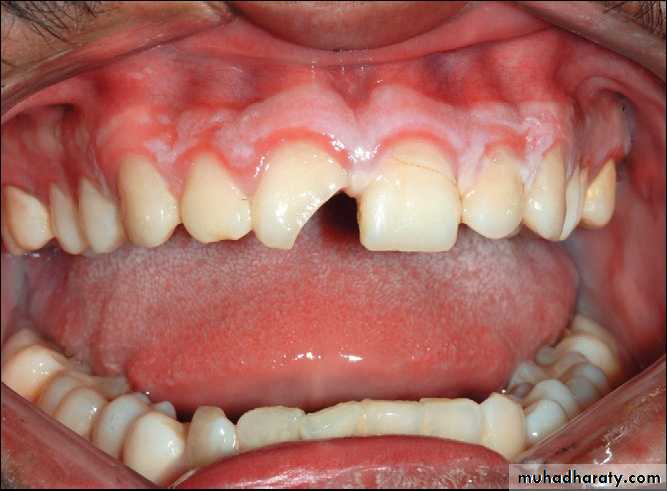

Primary contact in premolar region indicating an alveolar process fracture in the maxilla.

Platally displaced central and lateral incisors in apically mature tooth.

Position of teeth after digital reduction and stabilization with bonded arch wire.- Intrusion